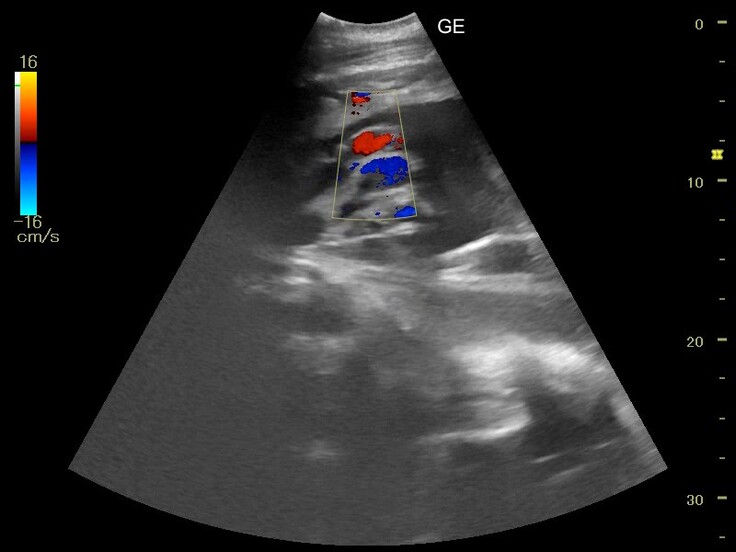

ですが、へその緒の様子は確認できました。

詳しくみてみたところ、へその緒の中にちゃんと血流があることも確認できました。

この結果から、胎児の心臓はちゃんと動いているだろうということが確認できました。